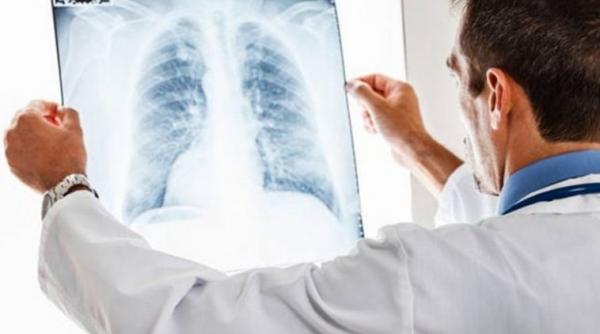

Halena arată bolile plămânului. Compuşii din aerul expirat pot indica dacă o persoană suferă de cancer pulmonar